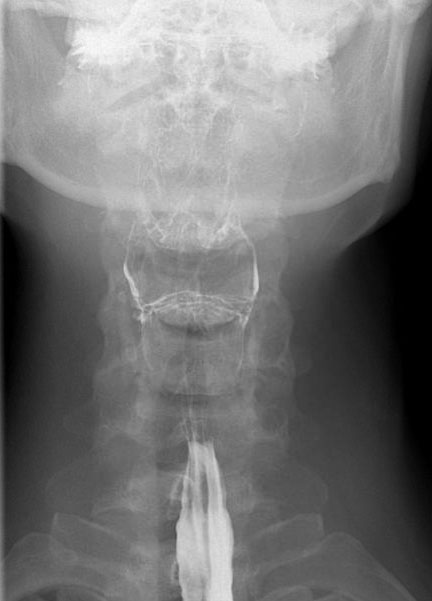

Tư thế thẳng (AP-view) quan trọng để đánh giá sự bất đối xứng.

Sau khi hoàn thành chuỗi hình ảnh giai đoạn hầu họng, cần theo dõi bolus thuốc cản quang toàn bộ đường đi xuống đến chỗ nối thực quản-dạ dày.